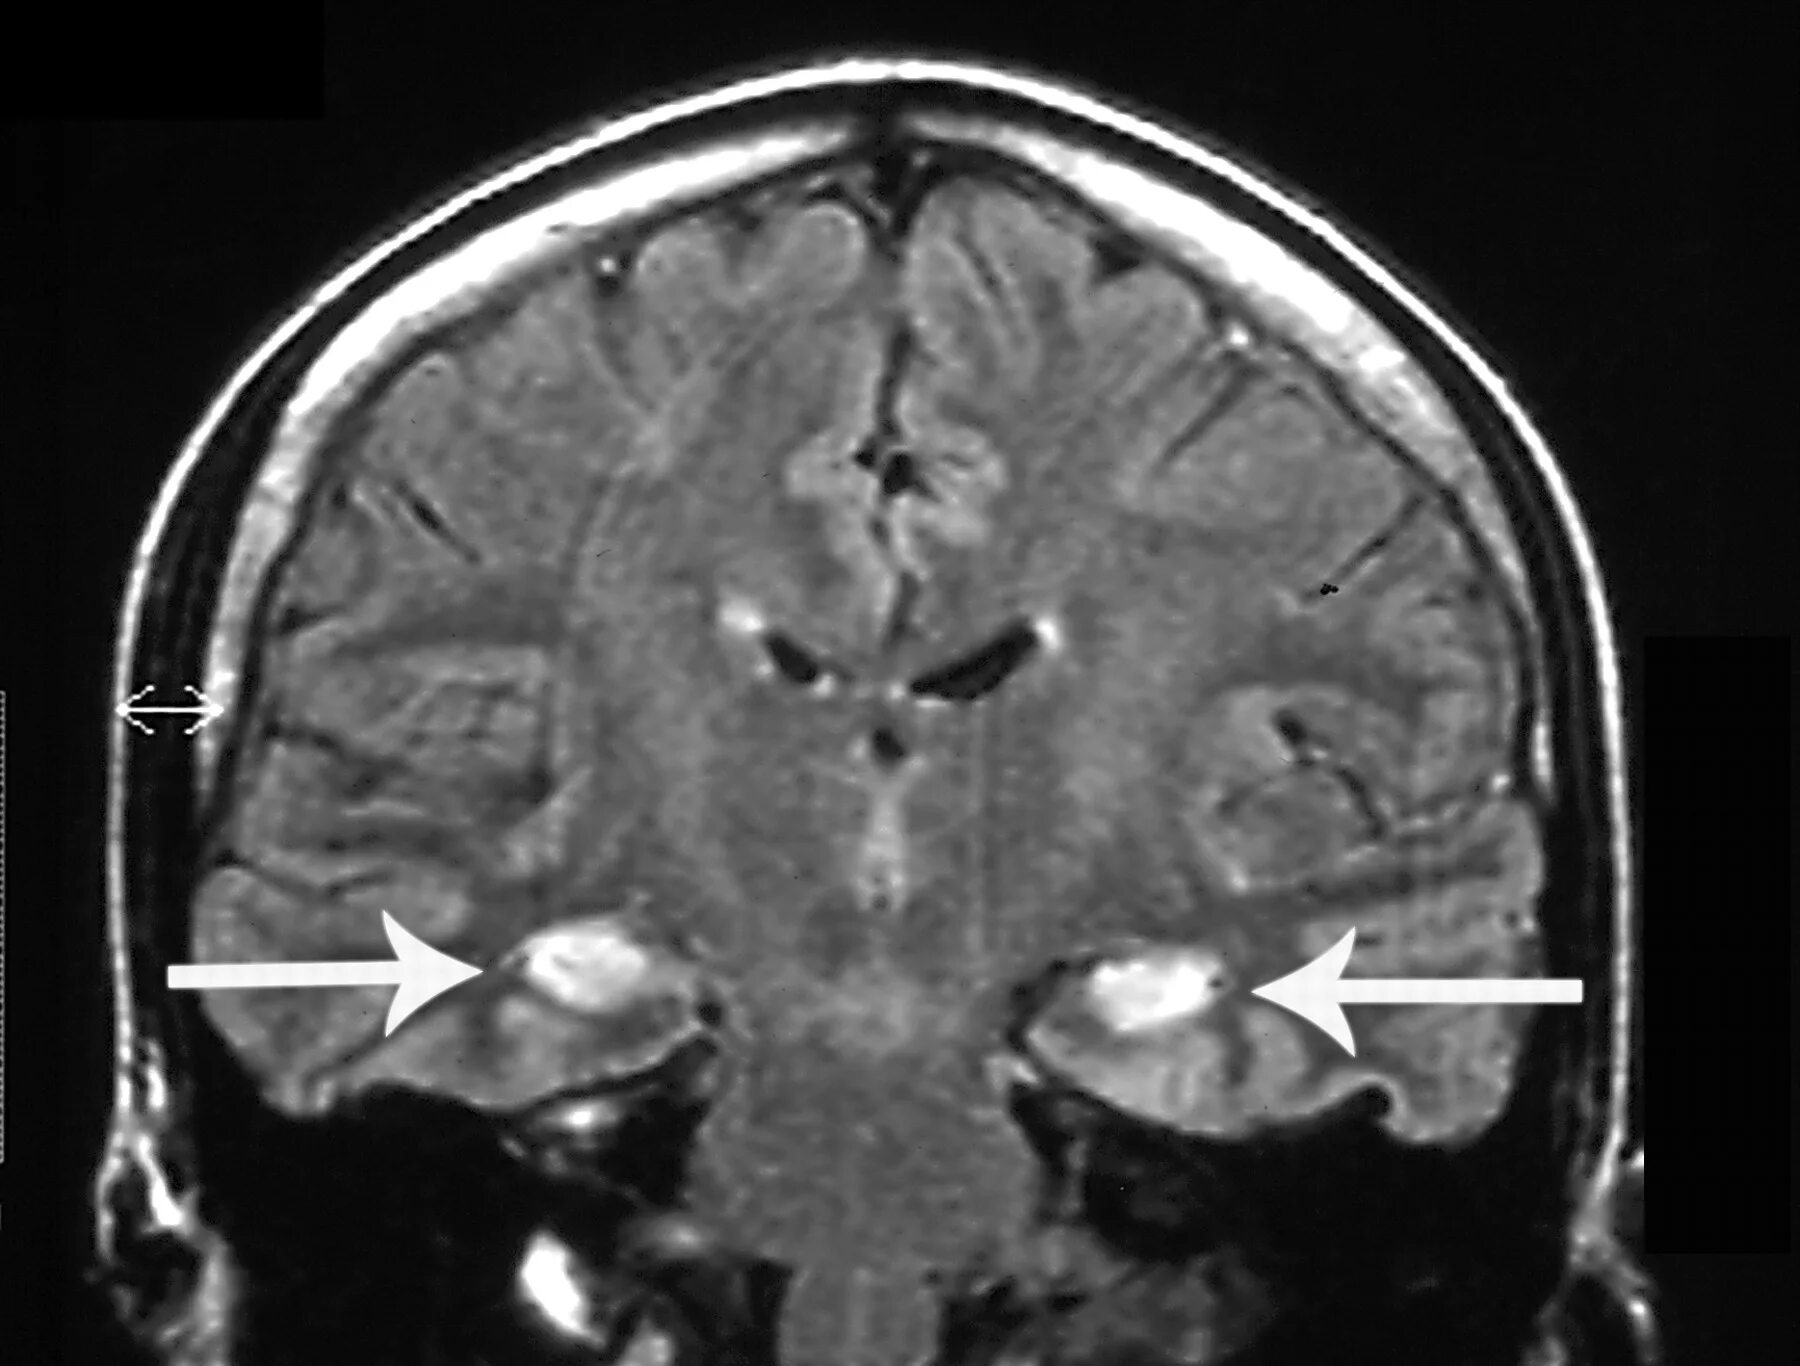

Энцефалит головного мозга симптомы у взрослых